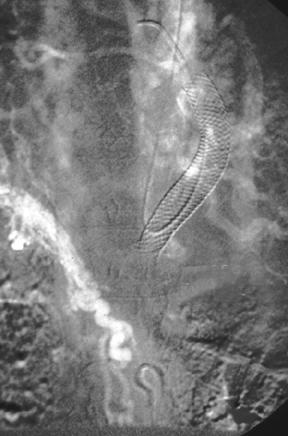

| The hepatic venogram views above and below reveal a transjugular intrahepatic portosystemic shunt (TIPS shunt) that extends from the hepatic venous outflow into the portal venous system in a patient with thrombosis from the Budd-Chiari syndrome. The shunt is blocked by thrombus, with no outflow. |